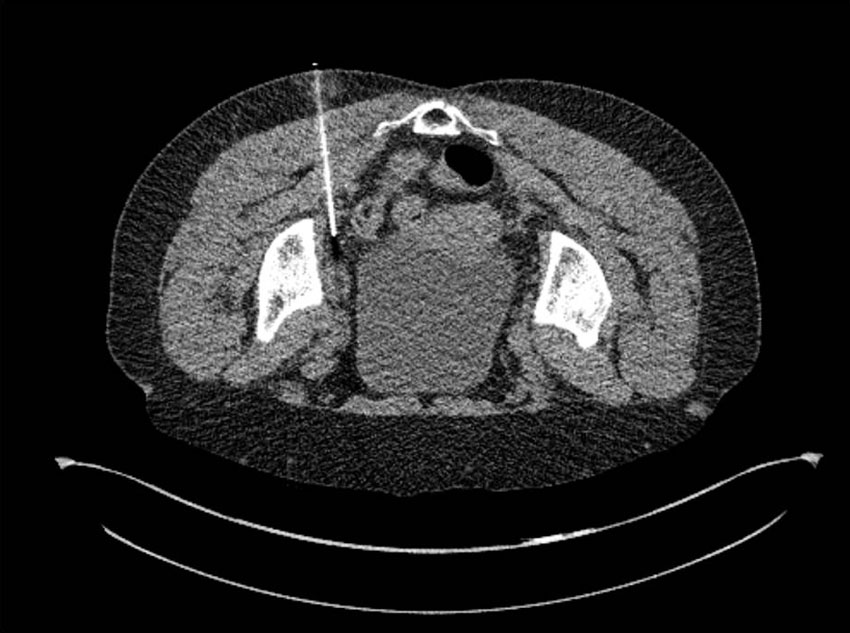

Datortomografiledd punktion i bukläge av patologiskt förstorad vänstersidig lymfknuta i lilla bäckenet. Lymfknutan visade högt upptag av fluorodeoxiglukos (FDG, se nedan) vid den PET-DT-undersökning som visas i figuren nedan.